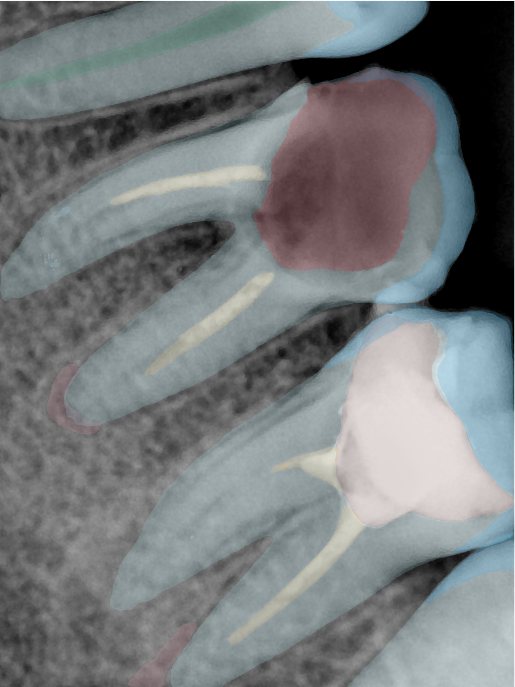

CR/DR 牙齿分割阶段记录

当前进展

- 完成了 CR/DR 牙齿相关分割训练

- 当前结果已经达到阶段预期,但仍有细节问题需要继续处理

相关测试

遇到的问题

- 训练过程中出现过 mask 下移问题

- 部分结果会出现 box 填充异常

- mask 边缘仍然有比较明显的锯齿感

第二版算法问题测试

| 第一版 | 第二版 | 是否解决 | |

|---|---|---|---|

![]() | ![]() ![]() 边角识别有问题 龋齿识别不全 牙髓识别不全 | ![]() | 解决 |

![]() | ![]() 边角识别有问题 识别信息有误 自查(牙冠识别不全) | ![]() | 解决 |

![]() | ![]() ![]() 边角识别有误 大范围填充识别遗漏 | ![]() | 解决 |

![]() | ![]() 识别信息不全 | ![]() | 解决 |

![]() | ![]() ![]() 边角问题 牙胶识别不全 牙冠识别不全 | ![]() | 解决 |

![]() 换图片 | ![]() | ![]() 牙冠部分稍微白了一些就识别成小范围修补,部分判断异常 | 部分解决,修复类略敏感,牙冠部分稍微白了一些就识别成小范围修补,部分判断异常。 |

![]() | ![]() ![]() 牙冠识别不全 牙髓不全 根尖炎龋齿识别有误 | ![]() | 解决 |

![]() | ![]() | ![]() | 解决 |

![]() 换图片 | ![]() | ![]() | 解决 |

![]() | ![]() 牙冠识别有误 | ![]() | 解决 |

![]() 换图片 | ![]() ![]() 边角识别有误 | ![]() 修复类敏感 | 部分解决,图像过白,导致修复类判断异常。 |

![]() 换图片 | ![]() 牙冠识别不全 | ![]() 修复类敏感 | 部分解决,图像过白,导致修复类判断异常 |

结论:修复类出现了不鲁棒的情况,后续需要加入轮廓的扩充数据进行增强。